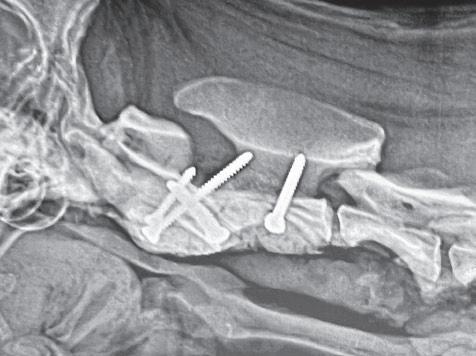

Tratamiento quirúrgico de la subluxación atlantoaxial 30

• Tratamiento quirúrgico de la subluxación atlantoaxial